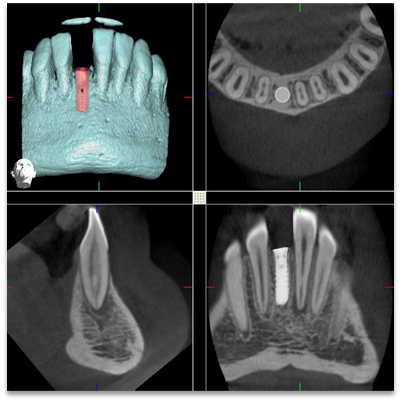

What are Dental Implants?

The Procedure

• Surgical placement of implants – including the use of grafts if required